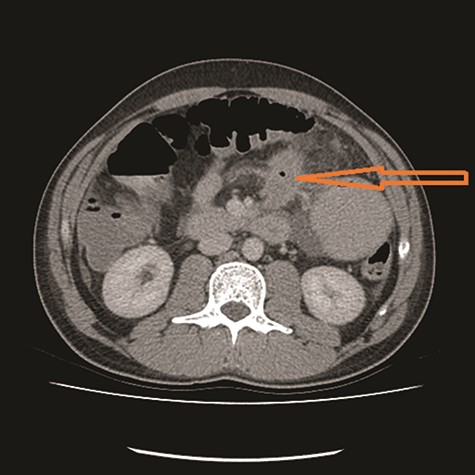

CT showed high-grade proximal jejunal obstruction secondary to a locally infiltrative jejunal mass (Fig. 1) suspicious for carcinoma. There was disseminated peritoneal carcinomatosis with a small volume of ascites and two hepatic metastases (Figs 2–4). A liver biopsy confirmed metastatic deposit of intestinal origin that was positive for CK20 and CDX2 and negative for CK7 and TTF1. There was a mutation in codon 61 of the NRAS gene with no sign of microsatellite instability. Diagnosis of jejunal adenocarcinoma was made.